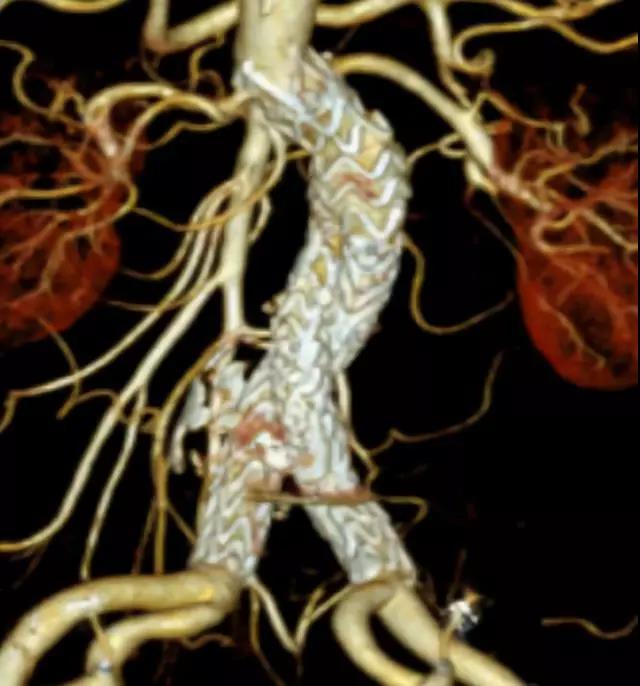

此次研究,纳入腹主动脉瘤的最大直径为85mm,平均直径为50.78mm;最短瘤颈长度为11mm,平均长度为31.34mm;最大肾下成角为74.6度,平均角度为32.48度。从动脉瘤最大直径变化来看,经过腹主动脉腔内治疗后,在出院前和术后6个月都有所减小。 在此次研究中,先健Yuranos™新一代腹主动脉覆膜支架系统临床试验初步展现了优秀的临床试验结果,其30天内MAE发生率低,安全性得以验证;而且由于该产品的柔顺性有较大提升,输送器直径减小,对于短瘤颈和角度大的病例是更好的选择。 入组病例展示: 病例一:男性,年龄69岁,既往高血压,糖尿病病史。术前腹主动脉瘤直径67.3mm,近端瘤颈长度23.2mm,近端锚定区直径21.2mm,肾下成角60.5度。 术中从右侧股动脉穿刺,选用先健型号为AB-2412-50-120的主体支架,支架近端定位于右肾动脉开口处,后释放打开裸支架,并向下释放主体短分支,左侧输送进入先健髂动脉延长支架IE-1416-100,并释放,保留左侧髂内动脉。接着释放主体长分支,右侧输送进入先健髂动脉延长支架IE-1424-80,并释放,保留右侧髂内动脉。 手术顺利,无内漏,持续时间1小时10分钟。术后CTA检查,支架形态良好,无内漏。详见下图: 术前影像 术中影像 出院前影像 术后6个月影像 术后1年影像 病例二:女性,年龄72岁,既往高血压,静脉曲张病史。术前腹主动脉瘤直径48.81mm,近端瘤颈长度16.15mm,近端锚定区直径18.43mm,肾下成角66度。 术中从右侧股动脉穿刺,选用先健型号为AB-2412-50-140的主体支架,支架近端定位于右肾动脉开口处,后释放打开裸支架,并向下释放主体短分支,左侧输送进入先健髂动脉延长支架IE-1414-120,并释放,保留左侧髂内动脉。接着释放主体长分支,右侧输送进入先健髂动脉延长支架IE-1414-80,并释放,保留右侧髂内动脉。

手术顺利,无内漏,持续时间1小时10分钟。术后CTA检查,支架形态良好,无内漏。详见下图: